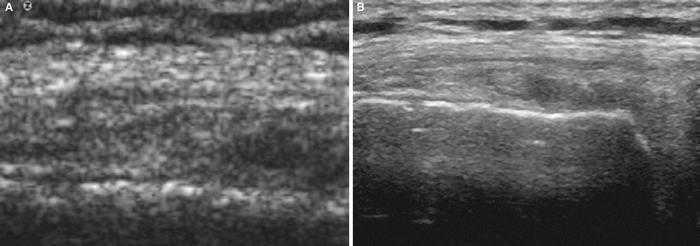

Utilizando el equipo E-A, mediante corte transverso sobre el músculo contusionado se observa (fig. 1A) la imagen de predominio hiperecoico y en su interior la zona oval hipoecoica con mala delimitación de los bordes y con mala definición del contenido, lo que la hace compatible con un lesión muscular por mecanismo extrínseco. La imagen del equipo E-B presenta también un aspecto hiperecoico, si bien la zona oval hipoecoica/anecoica presenta bordes muy bien marcados y se observa con detalle que en el interior existe un contenido heteroecoico que corresponde a las zonas de reabsorción del hematoma (fig. 1B). Todos estos signos permiten el diagnóstico preciso de la lesión muscular extrínseca.

Figura 1 A) En el corte transverso con E-A se observan imágenes hipoecoicas en el vientre del músculo gastronemio interno. B) En el mismo corte, con el equipo E-B se delimita exactamente la zona lesionada del área muscular indemne que lo rodea.